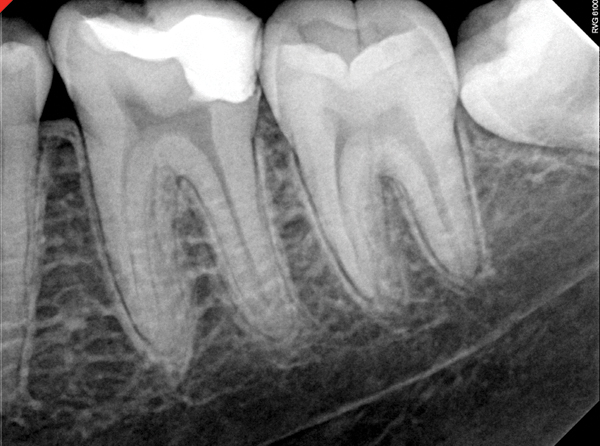

Fig 19. Preoperative radiograph of a case demonstrating apical periodontitis. Courtesy of Dr. Allen Ali Nasseh.

Figure 19

Fig 20. Immediate postoperative radiograph. Courtesy of Dr. Allen Ali Nasseh.

Figure 20

Fig 21. 5-year follow-up with complete healing. Courtesy of Dr. Allen Ali Nasseh.

Figure 21

This sealer solves most, if not all, of the previous problems of traditional sealers. Therefore, a thicker layer of sealer can be used because it is dimensionally stable and does not wash out. The core is used only as a hydraulic pump to move the sealer into place and allow for post space preparation or a pathway for retreatment. In addition and most importantly, the root canal preparation can be conservative and better adapted to restorative needs, since a traditional gutta-percha point (and not a metal plugger) is used to move the filling material. An additional benefit of the system is that there are now gutta-percha points that are impregnated with nano particles of bioceramics, so the sealer bonds not only to the root surface but also to the outer surface of the gutta-percha, eliminating the gap between the two (Figure 19 through Figure 21).